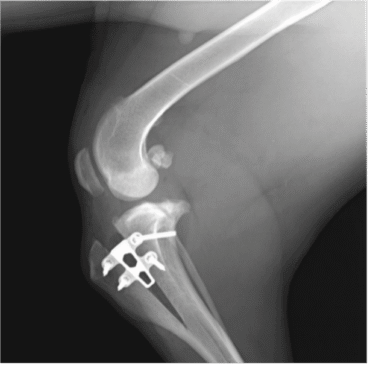

De TTA Rapid-methode

De TTA Rapid-operatie (Tibial Tuberosity Advancement) is een moderne chirurgische techniek die de knie weer stabiel maakt. Door een kleine aanpassing in het scheenbeen met behulp van een speciaal implantaat worden de krachten in het kniegewricht opnieuw in balans gebracht. Door deze verandering is de knie weer stabiel tijdens het bewegen. Deze methode passen we toe bij honden vanaf ongeveer 15 kg. Na herstel kan de hond weer pijnvrij en actief bewegen.

Röntgenfoto na TTA operatie